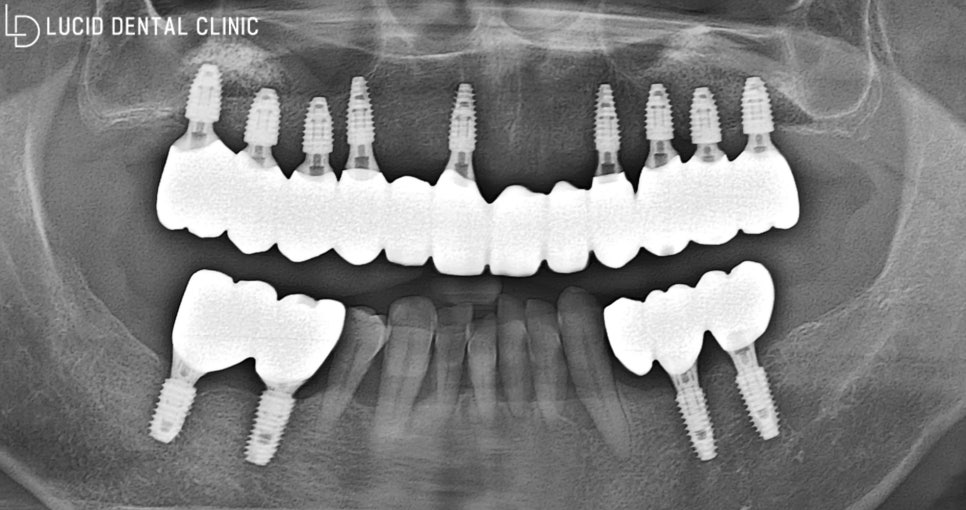

- 최종 종료

보다 빠르게 식립하고 치유할 수 있도록

가이드 보조 장치를 통해 진행했는데요

빠른 시간뿐만 아니라 통증 및 출혈을

최소화 할 수 있다는 장점이 있습니다.

아래 사진과 같이 임플란트 수술 을

안정적으로 마친 모습을 볼 수 있습니다.